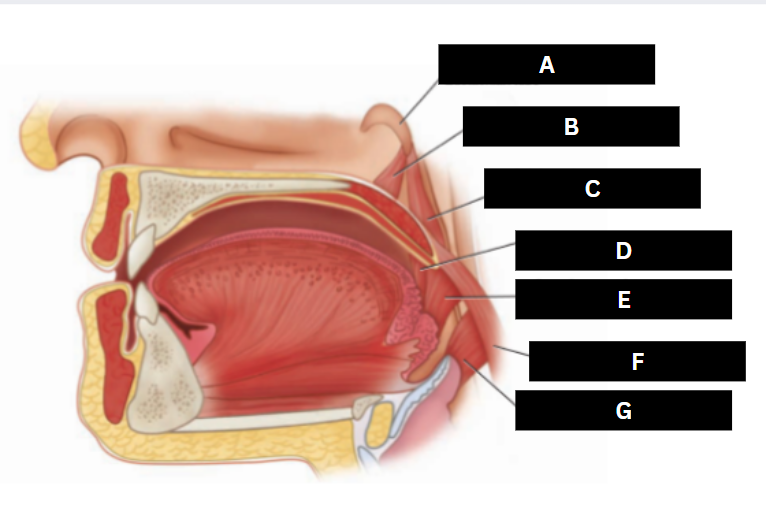

Eustachian tube

A

Levator veli palatini

B

Salpingopharyngeus

C

Palatoglossus

D

Superior pharyngeal constrictor

E

Palatopharyngeus

F

Middle pharyngeal constrictor

G